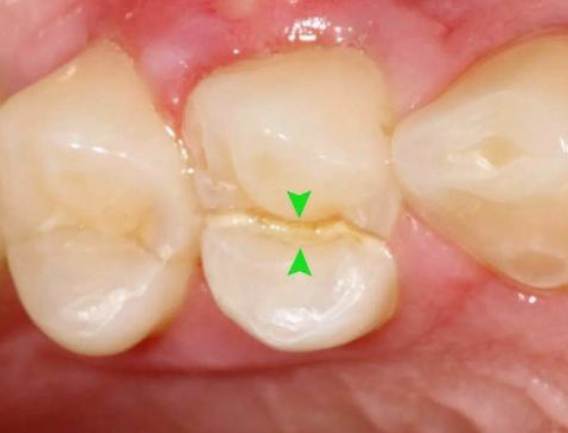

02、根管調(diào)節(jié)的適應(yīng)癥牙髓炎:牙髓因細(xì)菌感染而發(fā)炎。在密封的牙髓腔中,牙髓通常不會(huì)被細(xì)菌感染。當(dāng)牙齒因齲齒而開孔時(shí),該孔太深,外部細(xì)菌會(huì)侵入牙髓腔,從而感染骨髓。根尖周炎:牙髓感染細(xì)菌后,細(xì)菌將通過(guò)根尖孔侵入牙槽骨,導(dǎo)致根尖周圍組織發(fā)炎。只要去除感染的牙髓,根尖的炎癥就會(huì)消退。牙髓裸露:當(dāng)牙齒折斷并且牙齒的神經(jīng)暴露時(shí),通常需要進(jìn)行根管調(diào)節(jié)。03、根管調(diào)節(jié)的步驟1、術(shù)前拍攝X線片:在根管調(diào)節(jié)過(guò)程中,在根管調(diào)節(jié)術(shù)前拍X線片,可以幫助診斷,了解髓室的位置和根管數(shù)目及形態(tài),測(cè)量根管工作長(zhǎng)度。

于是抱著僥幸心理,讓牙齒在沒(méi)有“防護(hù)衣”的情況下:咬著小堅(jiān)果,嗑著小瓜子……有一天,“咔”!牙齒劈裂了!